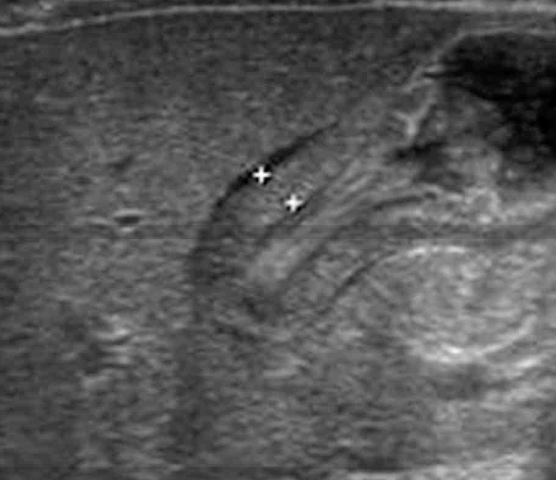

생후 1개월 된 남아가 3일 전부터 심하게 토해서 병원에 왔다. 구토는 생후 3주째부터 시작되었으며 점점 심해졌다고 한다. 구토물은 우윳빛이었으며, 토한 후에도 계속 먹으려고 한다. 배는 부드러우며, 덩이도 만져지지 않는다. 복부 초음파검사 사진이다. 진단은?

US: Thickened pyloric muscle

구토의 비담즙성 양상, 구토 후 계속 먹으려고 하는 점, 그리고 복부 US에서 비대해진 날문의 근육층이 관찰되므로 비대날문협착증을 진단한다.

• 복부를 만져보았을 때 특이 소견은 없으나, 초음파 검사상 두꺼워진 pylorus의 근육층이 저명하게 관찰된다.

• 구토의 비담즙성 양상, 구토 후 계속 먹으려고 하는 점, 그리고 복부 US에서 비대해진 날문의 근육층이 관찰되므로 비대날문협착증을 진단할 수 있다.

US: Pylorus 두께 > 4mm